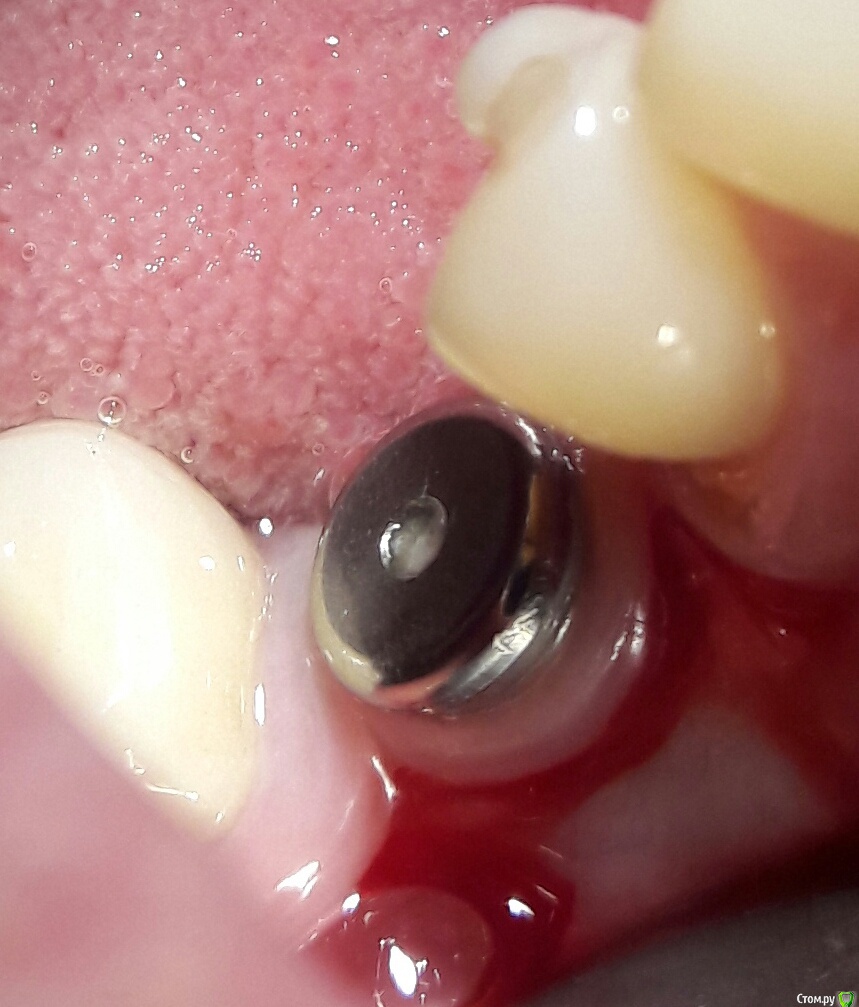

bilal Опубликовано 7 августа, 2016 Поделиться Опубликовано 7 августа, 2016 Помогите распознавать имплант. пациентка ставила 11 лет назад у другого доктора и уехала. Ссылка на комментарий

andr99 Опубликовано 9 августа, 2016 Поделиться Опубликовано 9 августа, 2016 Похоже на Straumann или на Blue Sky Bio, только не ясно,что с апексами.Нужной длины не было и решили подпилить?) Ссылка на комментарий

aka_sol Опубликовано 9 августа, 2016 Поделиться Опубликовано 9 августа, 2016 Похоже на Straumann или на Blue Sky Bio, только не ясно,что с апексами.Нужной длины не было и решили подпилить?)Точно не Straumann. 1 Ссылка на комментарий